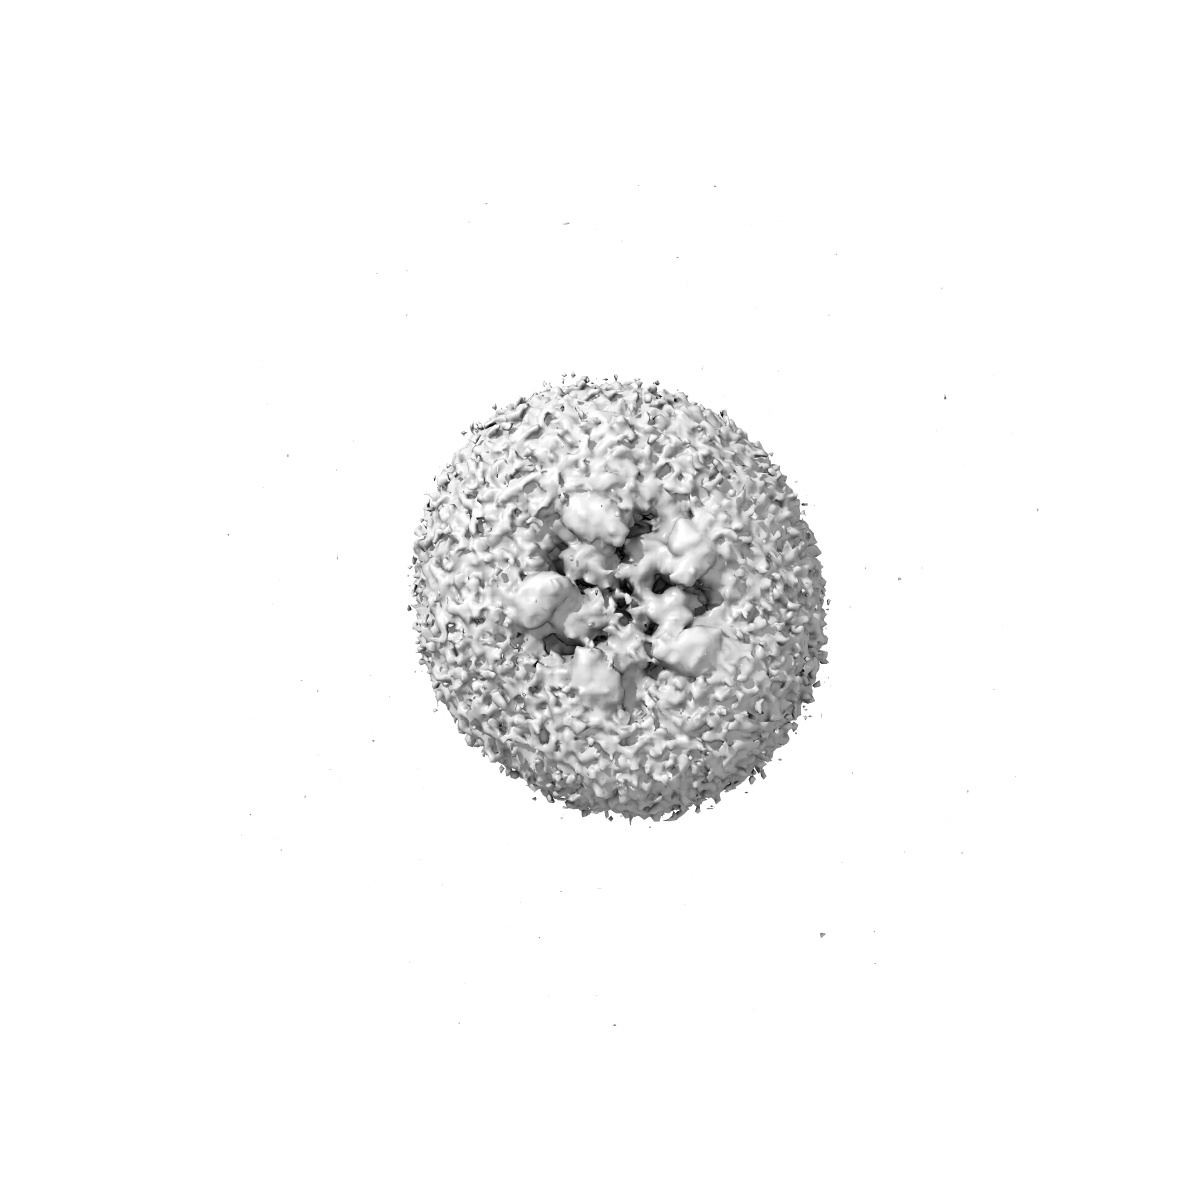

Cryo-EM structure of the beta3 homomeric GABA(A) receptor in complex with HSM in the short-lived symmetric bound-closed state (C1)

Sample: Cryo-EM structure of the beta3 homomeric GABA(A) receptor in complex with HSM in the short-lived symmetric pre-active state (C1)

Cryo-EM structure of the beta3 homomeric GABA(A) receptor in complex with HSM in the short-lived symmetric pre-active state (C1)

Deposition Authors: Mihaylov DB , Malinauskas T , Aricescu AR

Fitted models: 9fey